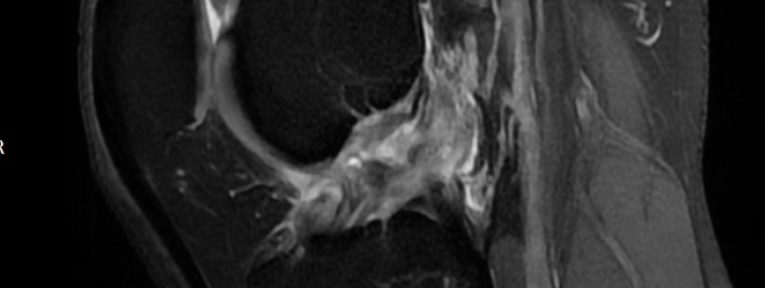

ACL Tear Natural Healing Case Report #50Case 50 | Natural Healing of Complete ACL Rupture: From Severe Ihara Type IV to Perfect Regeneration (ACLOAS Grade 0)